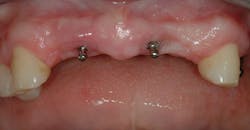

Figure 1 - Initial healing on two conventional diameter root form implants planned to help support and retain a mandibular complete denture.